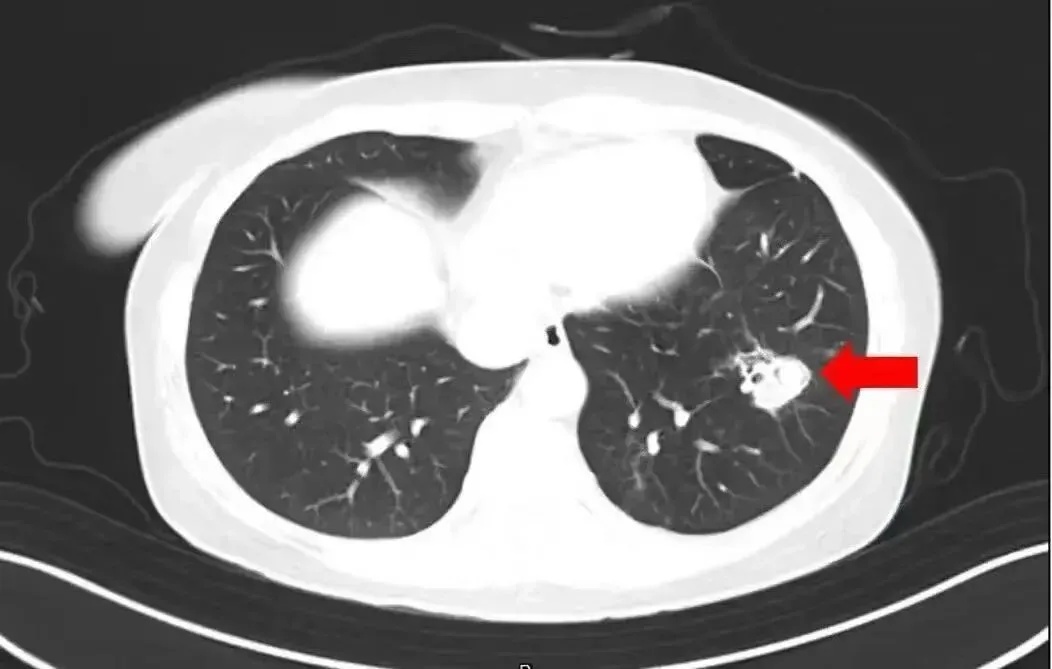

近日,一6岁女童因持续发烧17天且意识不清,被转至郑州大学第一附属医院治疗。医生检查后大吃一惊:孩子脑子竟被“啃”出大大小小十几个洞,再晚来几天可能会被“啃空”。抽取洞内积液检测后,医生锁定了“真凶”——烟曲霉菌。

医生介绍,烟曲霉菌常隐藏在潮湿环境中,孩子在此玩耍后,霉菌通过呼吸道进入血液系统,进而“爬”进了脑子。